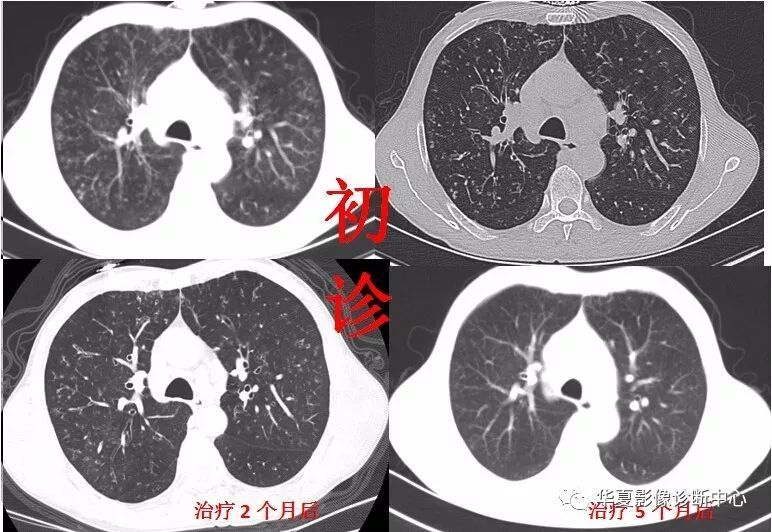

随着人们对健康的重视和低剂量螺旋CT的发展,越来越多的人检出肺结节。尽管如此,当很多人看到体检报告上“不能排除肺结节,北京四会西区医院中医肿瘤科钱艳芳主任说建议定期随访”的结论时,相信没有人不害怕,家住黑龙江的陈女士也不例外。陈女士今年55岁。2016年冬天,她因感冒咳痰。当地医院体检CT结果显示,肺结节呈斑片状,边界不清。医生建议随访。

2019年初,一个很冷的早晨,她感冒起床,咳嗽,痰中带血。在家人陪同下,到中国人民解放军总医院海南分院复查。CT结果显示左肺上叶纵隔及胸膜下见斑片,边界不清。双肺下叶增加一个直径约7mm的磨玻璃小结节,边界清晰。这次陈女士慌了,担心是肺癌。她想马上手术切除肺结节,但很多医生都拒绝了。医生说很可能是良性的,建议随访。